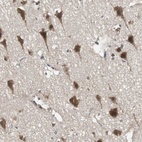

Immunohistochemical staining of human cerebral cortex shows strong cytoplasmic positivity in neuronal cells.